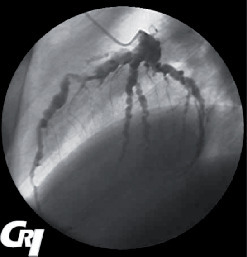

L’absence de traitement expose au risque de survenue d’anévrismes coronariens (fig. 7). Le traitement par acide acétylsalicylique (50-80 mg/kg/j lors de la phase aiguë, puis 3-5 mg/kg/j) et par immunoglobulines intraveineuses (2 g/kg en une seule dose) est rapidement efficace.